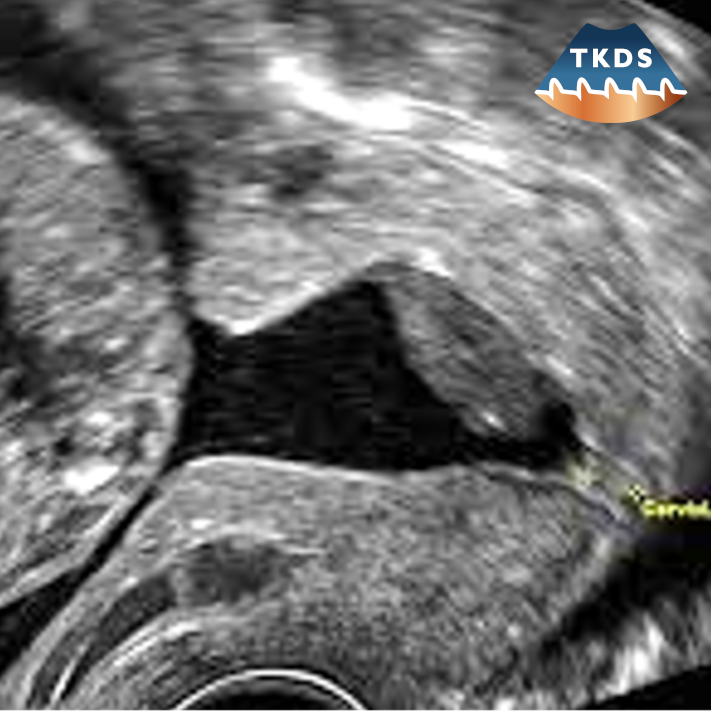

Die Dopplersonografie ist eine wertvolle additive Methode in der geburtshilflichen Ultraschalluntersuchung, der Sonografie des weiblichen Beckens und der Mammasonografie.

Als hochspezielisierte Untersuchung erfordert deren Anwendung zusätzliche Qualifikationen, verantwortungsvollen Einsatz ssowie kritischen Umgang mit den Ergebnissen und den aus diesen sich ergebenden Konsequenzen.